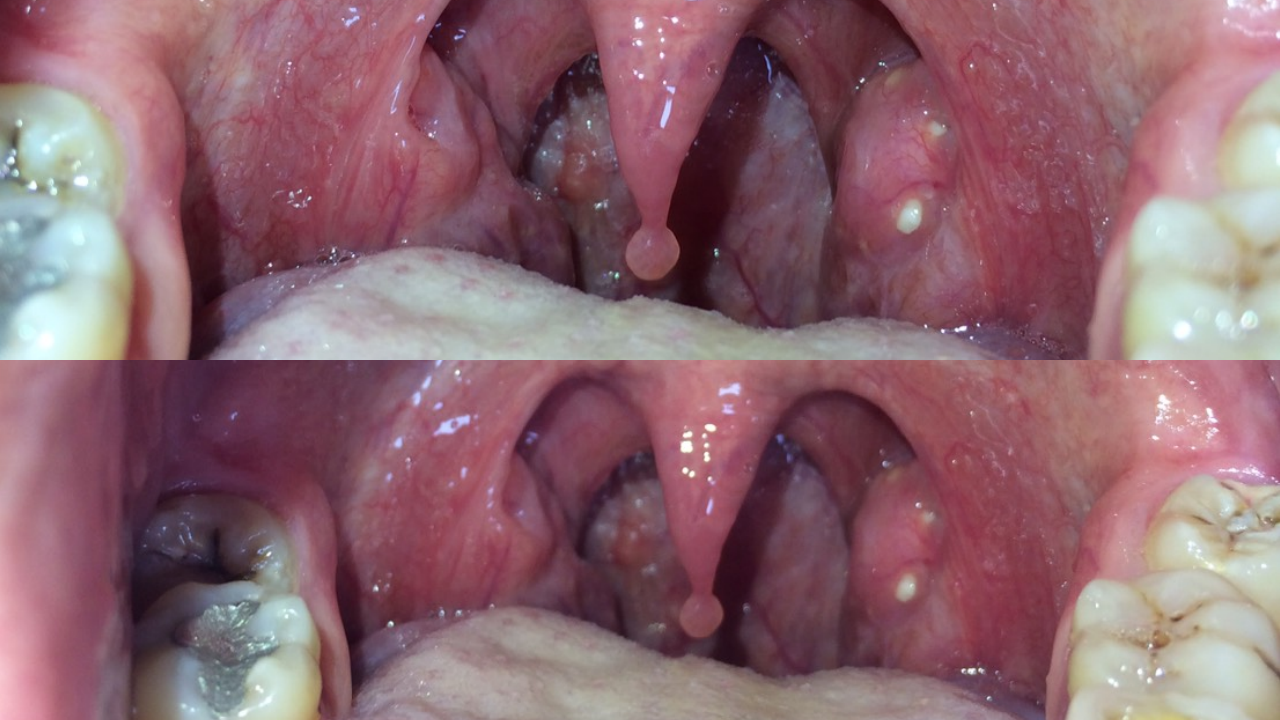

เพราะกลิ่นปากไม่ใช่เรื่องตลก!...ก้อนสีเหลืองอยู่ในคอ มีกลิ่นเหม็นรุนแรง บางครั้งก็หลุดออกมาเอง บางคราก็ฝังแน่นอยู่เช่นนั้น...ลองส่องไฟ มองผ่านกระจก ลองเช็กดู คุณมีไหม? ซึ่งเรากำลังจะบอกคุณว่า เจ้านี่แหละเป็นอีกหนึ่งตัวการสำคัญของปัญหากลิ่นปาก!

ผู้สื่อข่าว มีโอกาสได้พูดคุยกับนายแพทย์ผู้เชี่ยวชาญท่านหนึ่งจากโรงพยาบาลตา หู คอ จมูก ซึ่งนายแพทย์ท่านนี้ได้ให้ความรู้เกี่ยวกับ “ก้อนสีเหลืองอยู่ในคอ และมีกลิ่นเหม็นรุนแรง” ว่า ก้อนสีขาวเหลืองมีลักษณะเหมือนเนย และมีกลิ่นเหม็น อยู่ในหลุมลึกของบริเวณต่อมทอนซิลนั้นเรียกว่า นิ่วทอนซิล (Tonsillolith) หรือที่หลายคนอาจจะเรียกเป็นภาษาปากว่า ขี้ทอนซิล

“หลายคนอาจจะนึกว่า ก้อนสีเหลืองนั้น เป็นเศษอาหารตกค้างที่ติดอยู่บริเวณด้านในลำคอ แต่ความจริงแล้วไม่ใช่ เจ้าก้อนสีเหลืองนี้จะถูกสร้างขึ้นมาโดยธรรมชาติ และไม่มีอันตรายใดๆ ทั้งสิ้น แต่เจ้าก้อนนี้จะเป็นอีกหนึ่งตัวการสำคัญของปัญหากลิ่นปาก และอาจจะทำให้คุณเกิดอาการระคายเคืองได้” นายแพทย์จาก รพ.ตา หู คอ จมูก ให้ความรู้

ขอบคุณภาพประกอบจาก คุณชาตรี ทองทับทิม